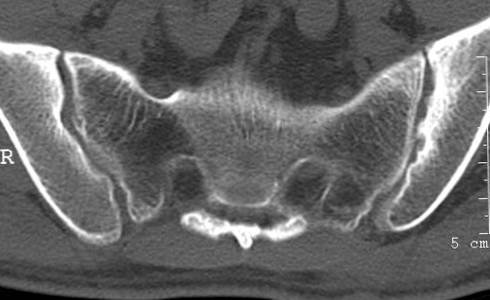

强直这种疾病,不少热分不清到底是属于哪种疾病,是骨科?还是中医科?大家都是比较的疑惑,也比较的迷茫。 其实严格的从病理来说,还是属于骨科,但在治疗中要看综合的治疗方式。我们知道,该病好发于青少年,这个年龄群体的发病率是很高的,另外这个病在初期病症并不明显,很容易造成患者的不知情或不注意,从而造成治疗的延迟,这是很重要的,一方面耽误治疗,一方面也未来的治疗带来很大的麻烦。因此养成定期体检是很好的习惯。